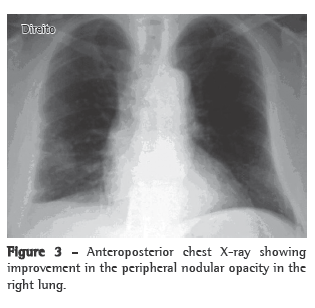

With treatment, the patient presented improvement of the clinical manifestations and the pulmonary alterations resolved (Figure 3).

DiscussionIn the present case, the patient had a nonspecific clinical profile and a significant history of smoking. The presence of pulmonary signs and symptoms in an elderly former smoker raises the possibility of lung cancer, due to its high prevalence and to the fact that it is a common condition, when compared with systemic vasculitis. Therefore, in the initial approach to this patient, lung cancer could not be ruled out. In view of this, we requested complementary tests that, in combination with the clinical manifestations, allowed us to make the diagnosis and define the best treatment.